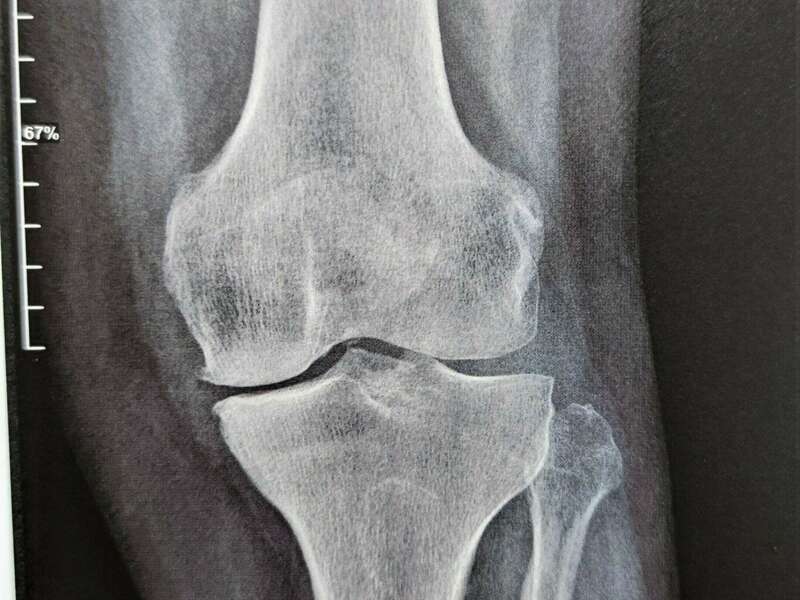

L’articulation du genou assure la jonction entre le fémur (condyles fémoraux), le plateau tibial et la rotule (patella). Elle se compose de deux articulations : l’articulation fémoro-patellaire entre le fémur et la rotule et l’articulation fémoro-tibiale qui elle-même se divise en deux compartiments (interne et externe).

L’arthrose désigne un processus d’usure du cartilage liée au vieillissement. Ce n’est pas une fatalité liée à l’âge. Elle cause des dommages irréversibles du cartilage qui perd au fur et à mesure son rôle de surface de glissement et d’amortisseur. La pression sur l’os s’accroît à mesure que l’épaisseur cartilagineuse diminue.

Des excroissances osseuses, appelées ostéophytes, des kystes osseux et des ulcérations cartilagineuses se forment progressivement. En réponse, la membrane synoviale devient inflammatoire et produit un liquide synovial. L’excès de pression articulaire et l’inflammation sont les causent des douleurs de genou. La perte de congruence de l’articulation entraîne quant à elle, une diminution de la mobilité articulaire.

L’arthrose n’entraine pas toujours des douleurs. On parle de dissociation radio-clinique : une arthrose visible radiologiquement n’est pas forcément responsable de douleurs. Dans ce cas, aucun traitement n’est nécessaire.

Elle sera confirmée par des examens radiologiques tels que des radiographies du genou. En cas de doute diagnostic ou afin de rechercher d’éventuelles lésions associées, un scanner et/ou une IRM pourront être prescrits.